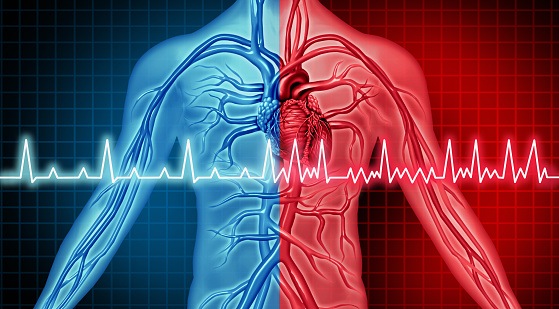

The joint execution of catheter and surgical ablation procedures is a nascent strategy in the treatment of patients with ...

Recently, high-power, short-duration (HPSD) strategies in radiofrequency ablation for atrial fibrillation (AF) have been ...

According to a recent study, led by Gang Yang, implementing additional low-voltage area (LVA) ablation alongside ...

Left atrial appendage preservation during surgical ablation for atrial fibrillation was not associated with an increased ...

In the DECAAF II randomized controlled trial, researchers evaluated the safety and efficacy of using magnetic resonance ...

Pulmonary vein isolation (PVI) via cryoballoon ablation (CBA) or radiofrequency ablation (RFA) is the standard treatment ...

According to a study, published in the Journal of Cardiovascular Electrophysiology, approximately 18% of patients with ...

Noting that previous studies on pulmonary vein (PV) atrial fibrillation (AFib) cycle length (CL) measurement returned ...

According to a study in Frontiers in Cardiovascular Medicine, alternative balloon-based approaches are effective ...

In patients with cardiomyopathy and ventricular tachycardia (VT), early catheter ablation near the time of implantable ...

A new study shows that intracardiac echocardiography (ICE) and its integration into three dimensional (3D) ...

Detecting atrial fibrillation (AFib) following an ischemic stroke (IS) is important, but in patients who suffer IS ...